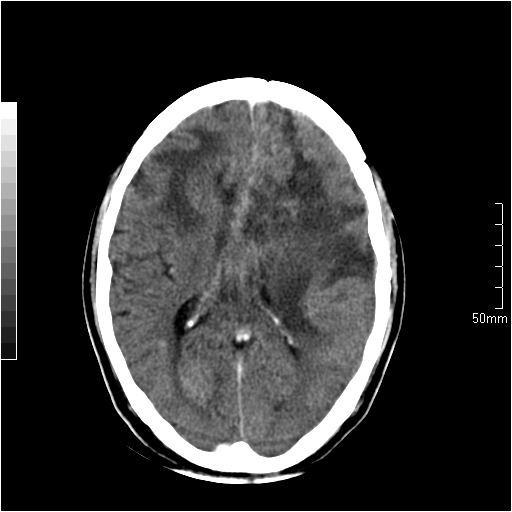

以下是引用天南地北在2007-6-25 12:39:00的发言:[br]有占位效应[br]支持术后复发

以下是引用zjzjr在2007-6-25 12:38:00的发言:[br]左侧复发,右侧转移。